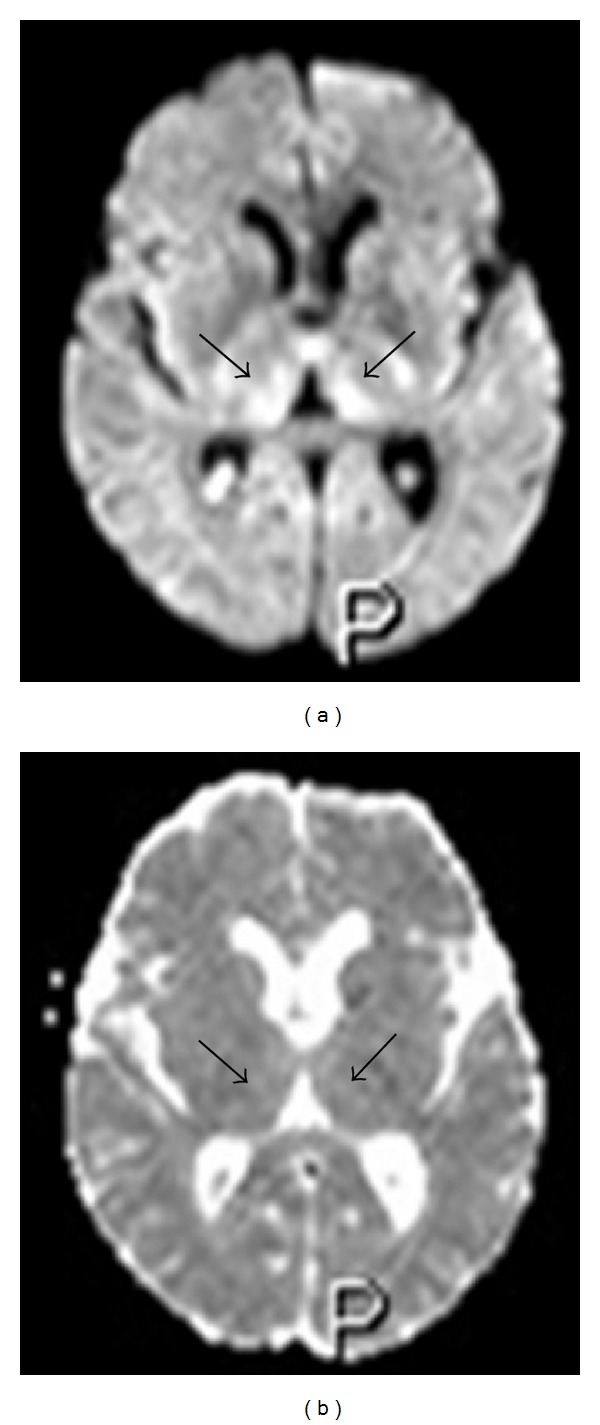

Figure 6.

Fifty-three-year-old man in total parenteral nutrition. Axial diffusion-weighted image (a) showing bilateral and symmetric high signal at the level of the medial portion of the thalami with normal ADC values (b), indicating the presence of vasogenic edema.

Figure 7.

Forty-seven-year-old woman with a 16-year history of alcohol abuse. Axial diffusion-weighted image (a) showing bilateral and symmetric high signal at the level of the medial portion of the thalami with reduced ADC values (b), indicating the presence of cytotoxic edema.